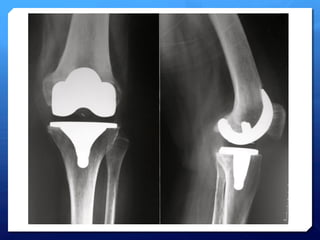

Gonarthrose

tri-­‐compartimentale

• 8.

• 9.